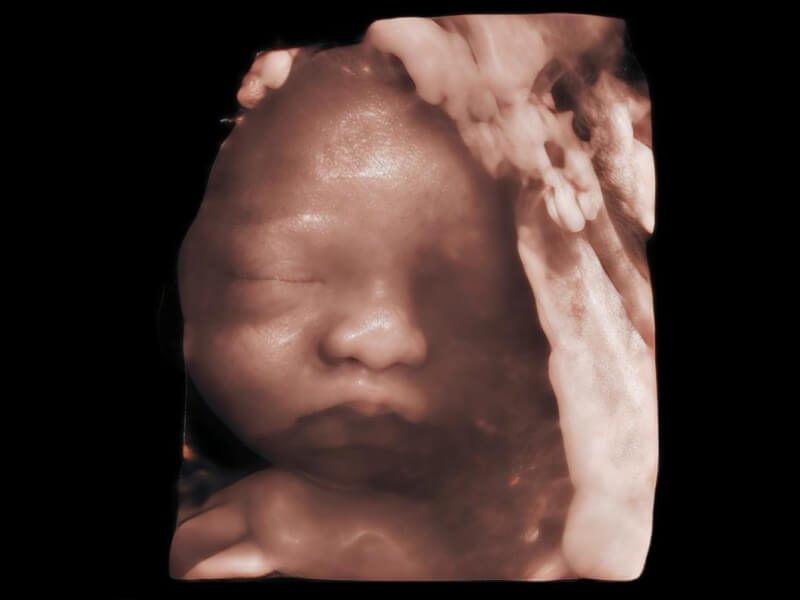

夢(mèng)溪?P80以“關(guān)愛(ài)女性”為基石,提供全方位的解決方案,量身定制以滿(mǎn)足女性的健康需求,涵蓋婦科、生殖健康檢查、產(chǎn)前篩查及產(chǎn)后康復(fù)等領(lǐng)域。